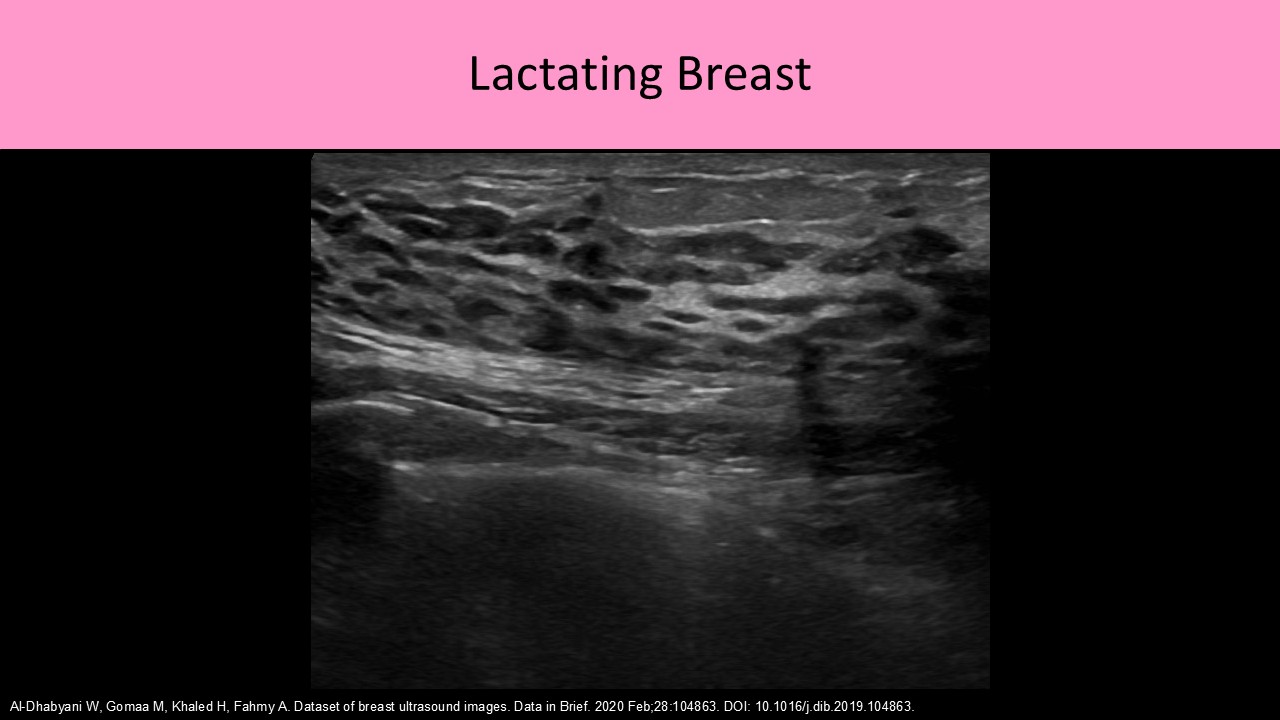

- Normal ducts in a lactating female should measure <8mm diameter